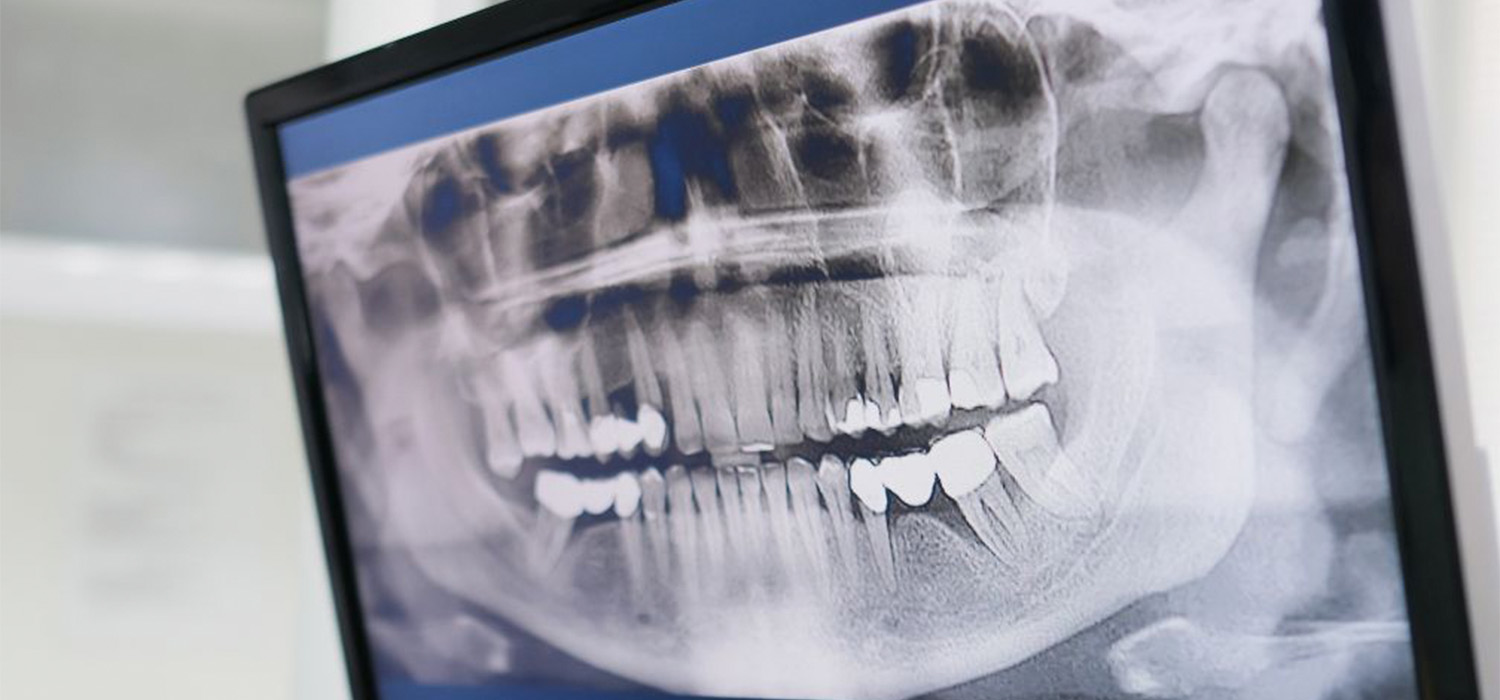

Did you know we offer OPG scans at our Leeton Practice. An OPG, or dental X-ray, is a great way to get a detailed assessment of your dental health.

An OPG (Orthopantomogram) is a panoramic X-ray of the upper and lower jaws, including the teeth.  The scan will provide your dentist or orthodontist with a clear indication of the positions of all your teeth and their growth.

OPG scans are quick and easy, and they give us a clear picture of your teeth and jaws. They can help us diagnose problems such as tooth decay, impacted teeth and tumors.